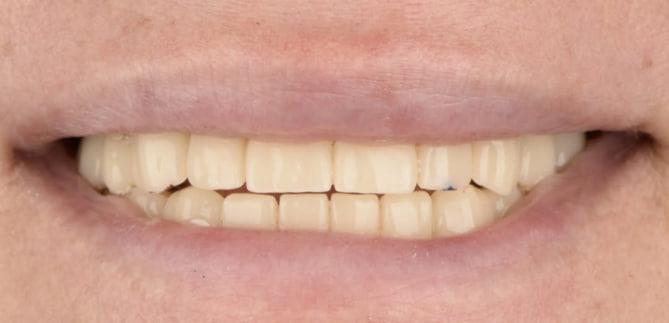

Тотальна реабілітація з функціональною діагностикою

Михайло, 50 років

Біль та запалення в ділянці зубів верхньої щелепи, часткова втрата зубів, виражена стираємість, порушення функції жування та дисбаланс у роботі зубощелепної системи.